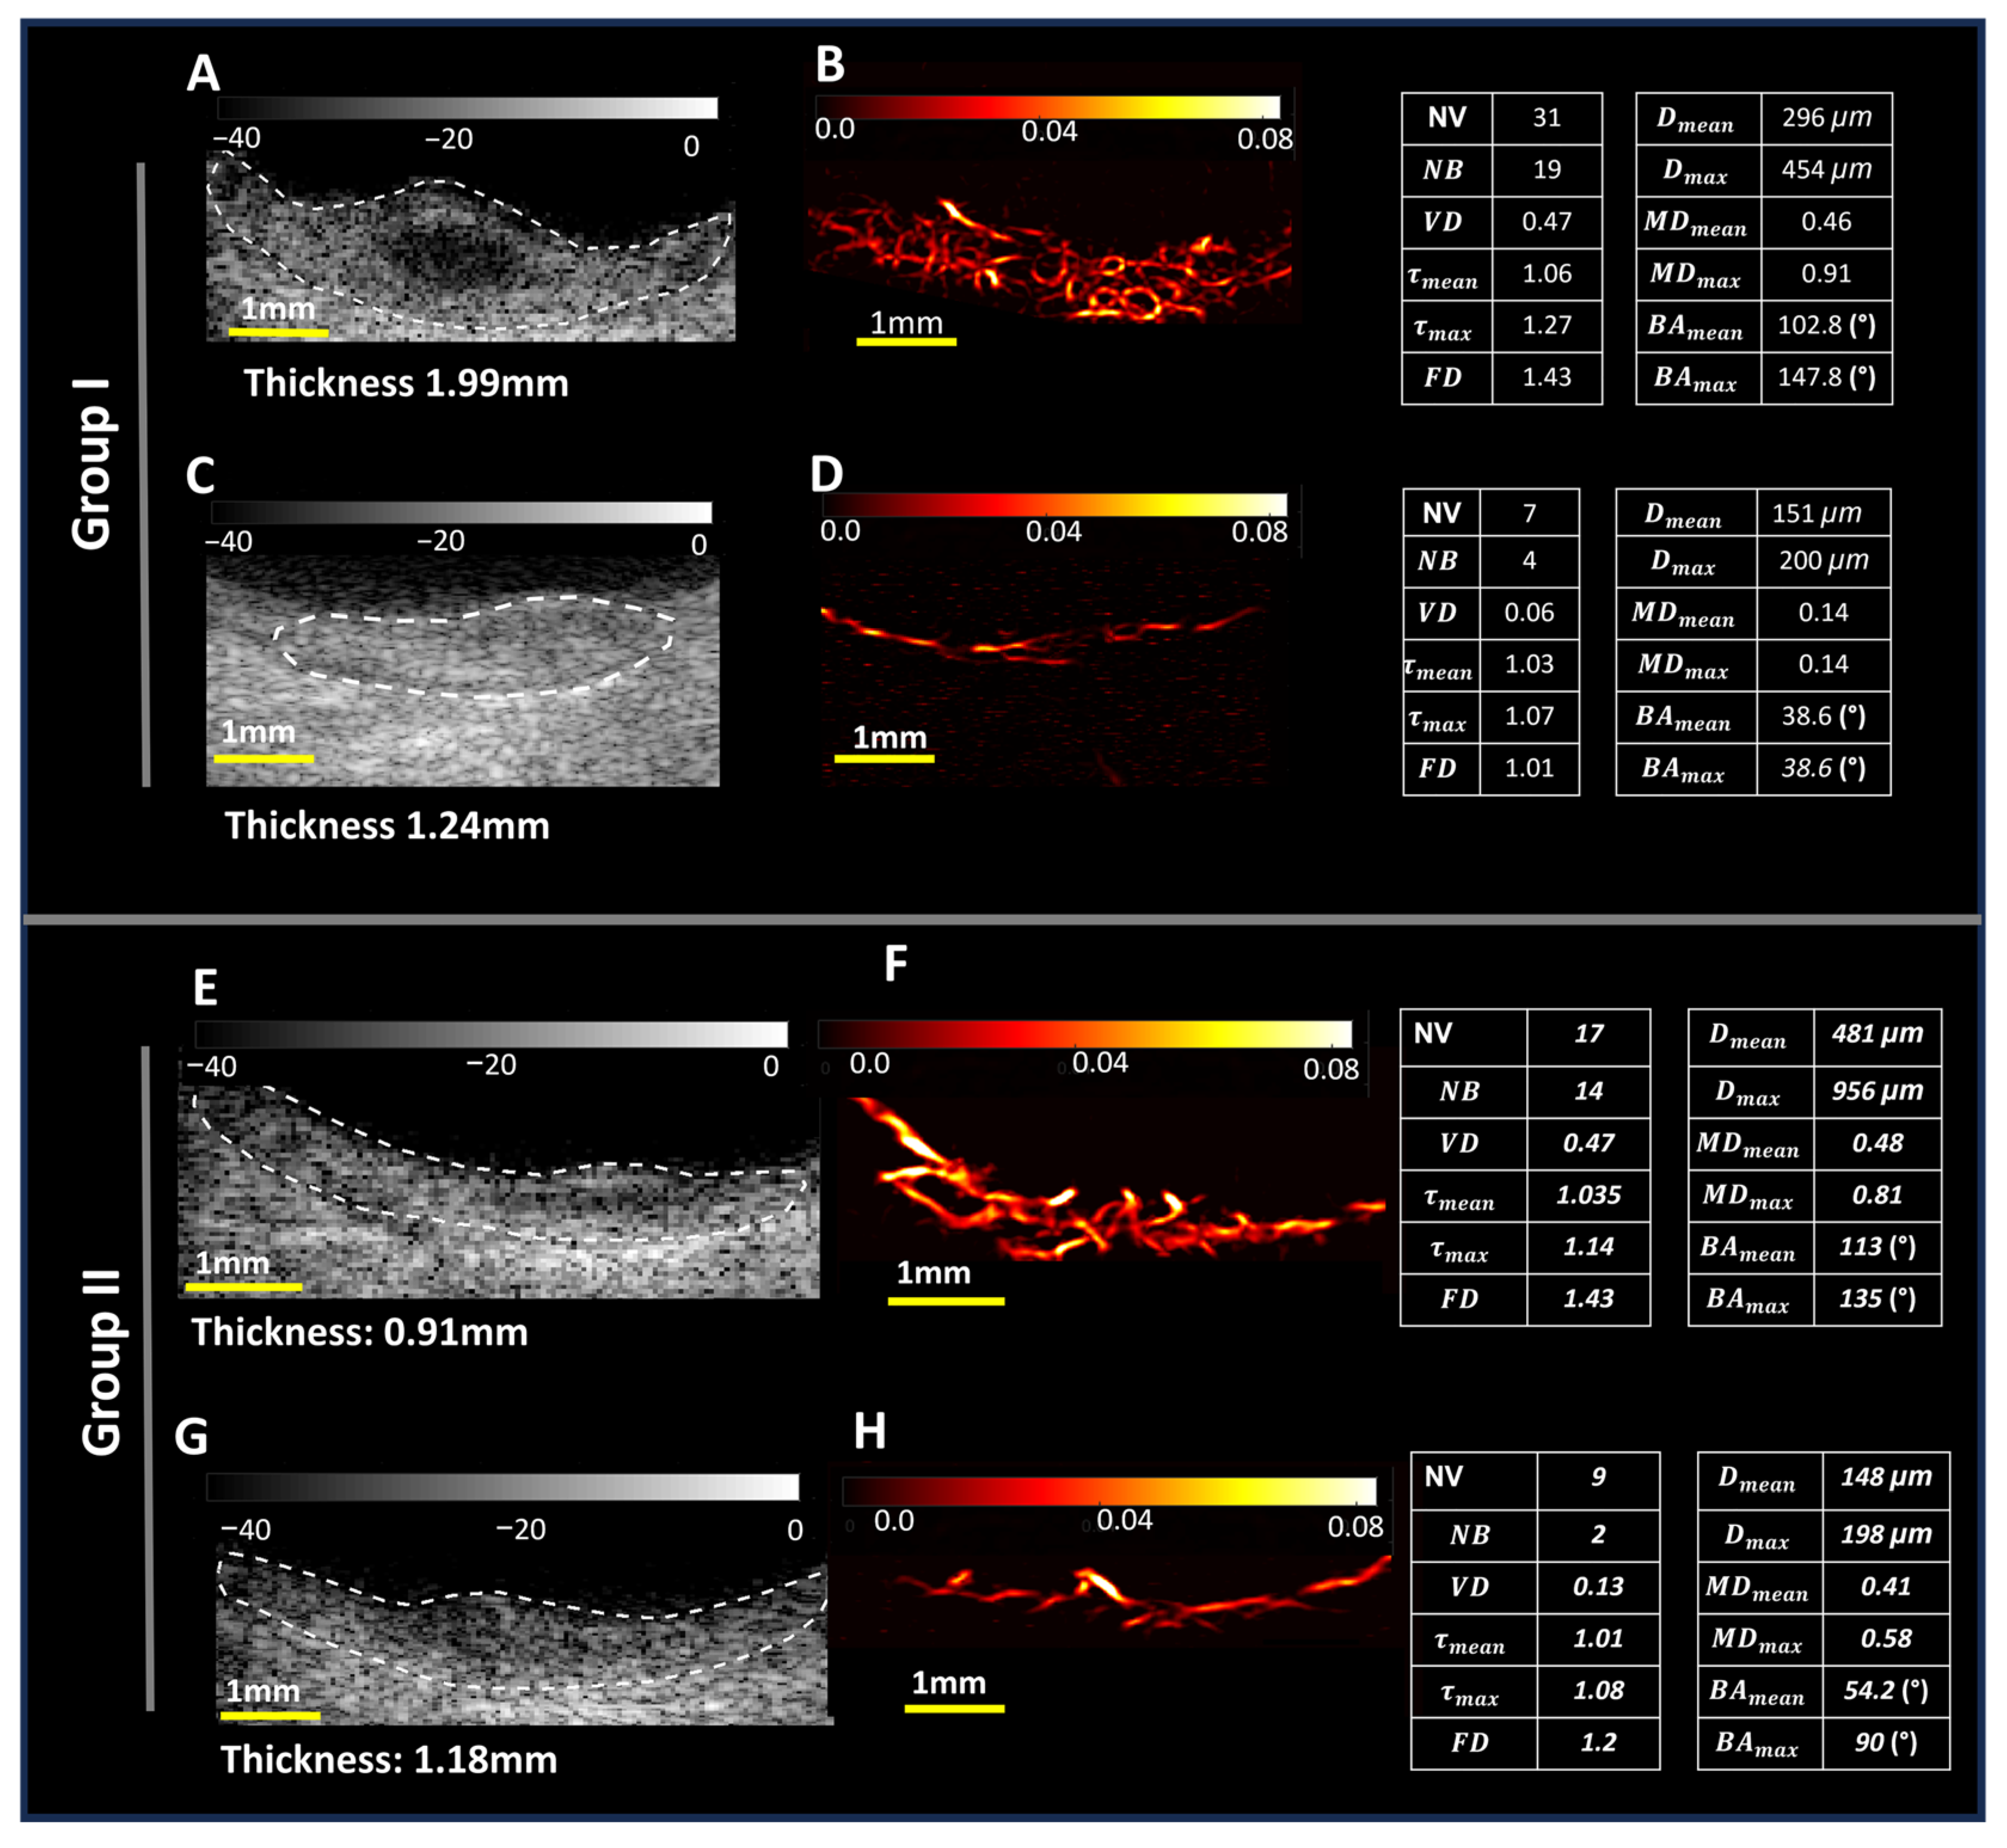

3.2. Microvessel Visualization and Quantification